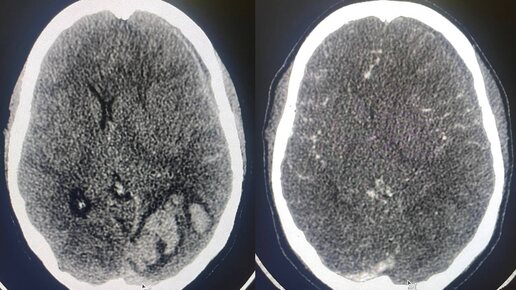

Центральный венозный тромбоз встречается реже артериального, но забывать о нём из - за этого не стоит, внимательно проверяя и венозную фазу

сканирования тоже, особенно при наличии внутримозговой гематомы - которая является одним из непрямых его признаков. На МСКТ: фрагментированная внутримозговая гематома в левой затылочной доле головного мозга. САК. ВЖК. Субдуральная гематома вдоль левого полушария головного мозга с распространением вдоль межполушарной щели и намёта мозжечка слева. Дислокация срединных структур. КТ - признаки формирующегося отёка вещества головного мозга. Дефект контрастирования поперечного, сигмовидного синусов слева и дистального отдела левой внутренней яремной вены...